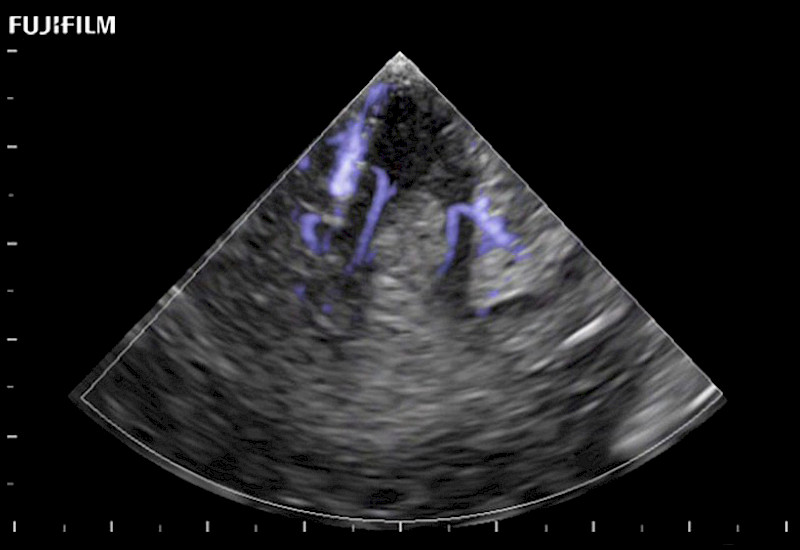

Exclusive 10mm side‐fire linear array transducer with 2.87mm diameter is ideal for real‐time visualization through and behind structures and instant, scalable definition of anatomy and vascularity including the ability to delineate and define tumor margins.

Guidance is the fundamental purpose for all of our surgical ultrasound technology. Fujifilm Healthcare is committed to designing tools that help neurosurgeons navigate inside the human body and provide the necessary information to immediately make critical surgical decisions.